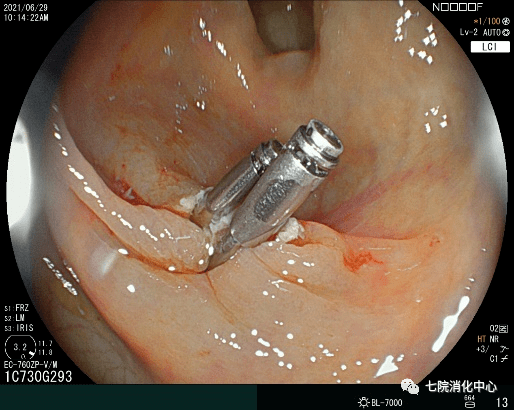

1、活检钳息肉切除

包括冷活检钳息肉切除术和热活检钳息肉切除术 , 活检钳通常用于切除5mm以下的结肠息肉 。